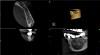

The second case study is that of a healthy 88-year-old woman who presented with significant bone loss on the mesial and apical aspect of tooth No. 18, which would suggest potentially a vertical fracture in the tooth (Figure 9 and Figure 10). The clinician had initially recommended extraction, which they informed the patient would likely be the best course of action, especially given that she had plenty of bone anterior to the tooth to place implants. When the recommendation of extraction was made to the referring dentist, he had some resistance because both he and the patient were interested in saving the tooth. Although the clinician initially stood firm on the recommendation, he received a call from the general dentist about a month later. He further expressed their desire to save the tooth, and he asked if the endodontist thought the new technology, the GentleWave Procedure, could be a solution. The informed consent was obtained and the patient was scheduled for treatment. Because the canal was quite calcified apically, a defined working length could not be determined. Obturation was performed using warm vertical condensation of gutta-percha.

Fig 9. Case 2: Significant bone loss on the mesial and apical aspect suggested a potential vertical fracture (Fig 9 and Fig 10). Radiographic images were taken immediately postoperatively (Fig 11) and 7 months postoperatively (Fig 12).

Figure 9

Fig 10. Case 2: Significant bone loss on the mesial and apical aspect suggested a potential vertical fracture (Fig 9 and Fig 10). Radiographic images were taken immediately postoperatively (Fig 11) and 7 months postoperatively (Fig 12).

Figure 10